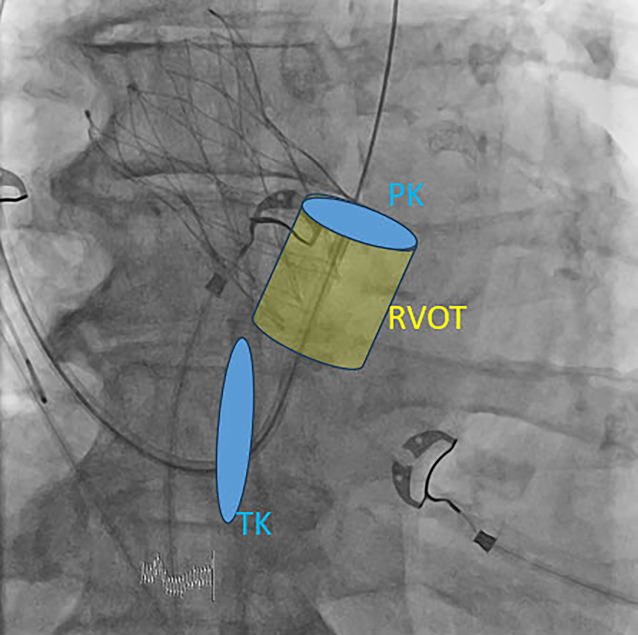

Left bundle branch area pacing is currently the most common form of physiological pacing prior to His bundle pacing. It is intended to prevent or correct the development of pacemaker-induced cardiomyopathy and is being used more and more frequently. In order to be able to perform this successfully, knowledge regarding the specific anatomy and radiological anatomy as well as the ECG criteria for left bundle branch pacing is required in addition to knowledge of the tools. In this article, the technical requirements and steps for successful implantation are summarized and pitfalls are highlighted.